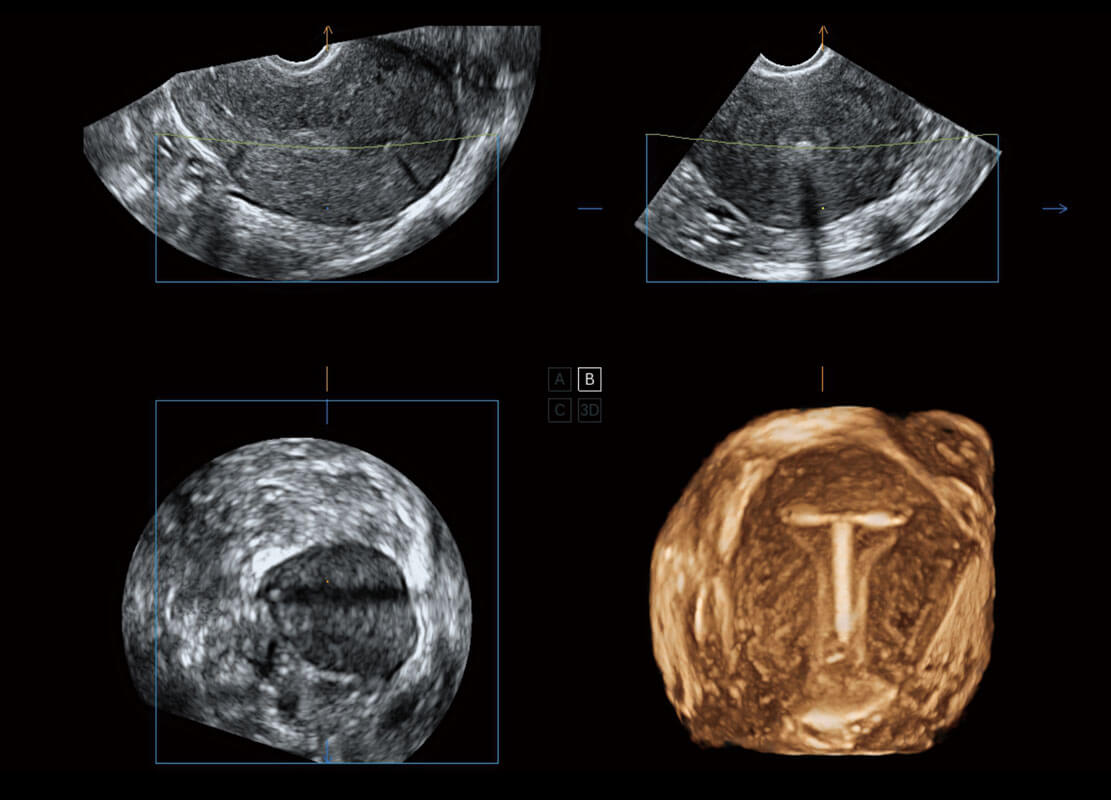

腔内三维-宫内节育器

腔内三维-光影成像